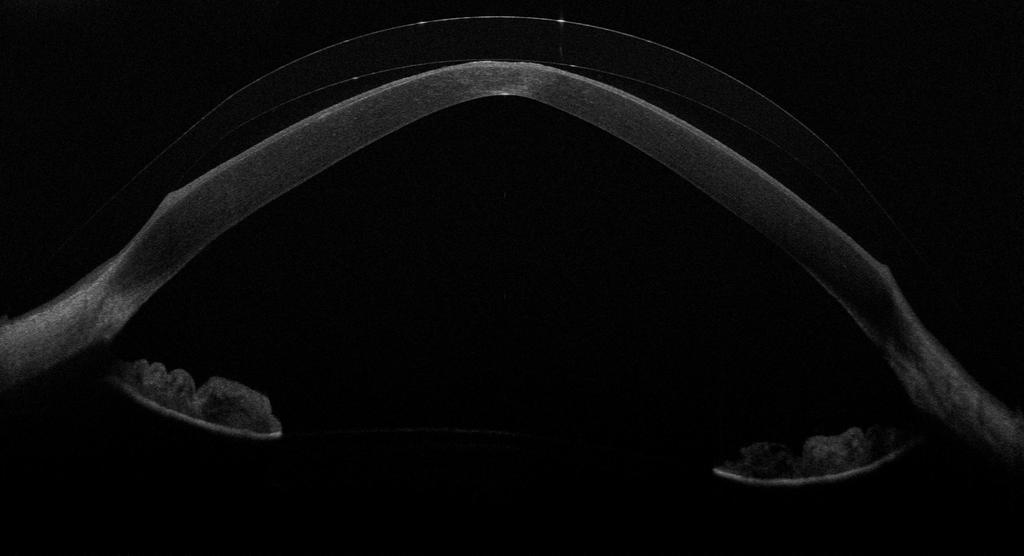

Das OCT – die Optische Kohärenztomographie – macht genau diese Befunde zugänglich. Es erzeugt einen hochauflösenden Querschnitt durch das vordere Auge: Linse, Tränenreservoir, Hornhaut – alles in einem Bild, im Mikrometerbereich aufgelöst.

Und hier das Gegenbild: Der zentrale Abstand hat sich deutlich verringert. Ohne OCT wäre diese Veränderung unentdeckt geblieben – der Patient hatte keine Beschwerden, die Spaltlampe war unauffällig. Erst der OCT-Scan zeigt: Die Clearance reicht nicht mehr aus.